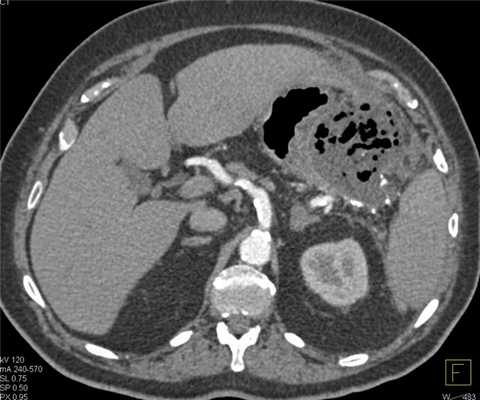

Гнойные осложнения острого панкреатита. Абсцесс поджелудочной железы. Большое, относительно хорошо отграниченное гетерогенное образование в области хвоста поджелудочной железы, содержащее пузырьки газа.